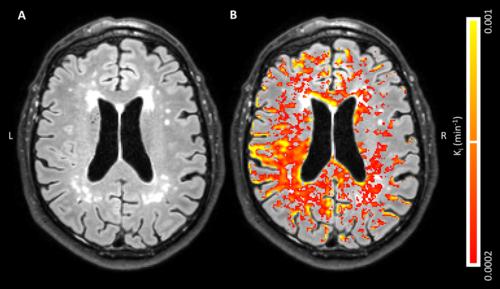

Global, diffusely distributed blood-brain barrier (BBB) leakage in patients with early Alzheimer’s disease (AD) suggests that a compromised BBB is part of the early pathology of AD and might be part of a cascade of pathologic events that eventually lead to cognitive decline, according to new Radiology research.

Harm J. van de Haar, MSc, of Maastricht University Medical Center in Maastricht, the Netherlands, and colleagues found that the BBB leakage rate was significantly higher in patients compared with that in control subjects in the total gray matter and cortex. For this pilot study, 16 patients with early AD and 17 healthy age-matched control subjects underwent dynamic contrast material–enhanced MRI sequence with dual time resolution for 25 minutes.

Patients had a significantly higher volume fraction of the leaking brain tissue in the GM, normal-appearing white matter, deep gray matter and cortex. When all subjects were considered, scores on the Mini-Mental State Examination decreased significantly with increasing leakage in the deep gray matter and cortex.

“We found an increased BBB leakage rate in the gray matter of patients with early AD. By also showing very subtle BBB impairment in the white matter, leakage volume proved to be even more sensitive to the differences in BBB leakage than was the leakage rate,” the authors write.